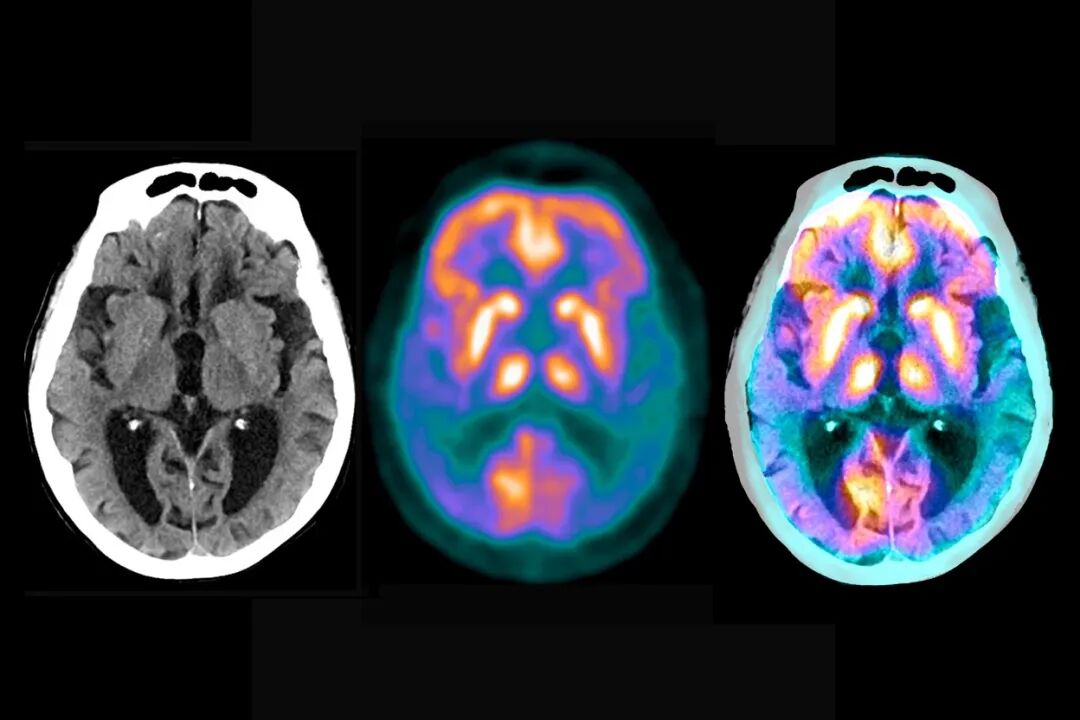

一种 MRI 扫描(人工着色)显示阿尔茨海默病患者的大脑。图片来源:Mark and Mary Stevens Neuroimaging and Informatics Institute/Science Photo Library

机器学习方法检测阿尔茨海默病的准确率超过 90%